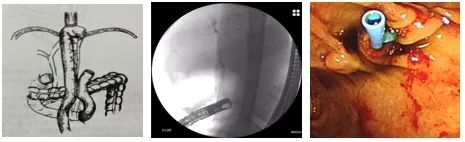

考虑到以上困难点,北京佑安医院消化中心二科李磊主任医师带领胰胆疾病内镜诊疗主诊组进行充分的术前讨论,制定相应手术策略, 2022年7月8日上午在消化中心主任丁惠国教授的指导下,李磊主任医师带领护士张丽、医师刘远志应用PCF-H290DI结肠镜寻腔进镜寻找十二指肠输入袢,仔细辨认乳头位置;直视镜下尝试插管困难,退镜留置导丝用于再进镜时引领方向、辨识十二指肠旷置端,再换用十二指肠侧视镜寻导丝进至十二指肠输入袢,确认乳头位置后,以反方向插管法将导丝和造影管置入胆总管,造影后可见肝外胆管狭窄,肝内胆管扩张,诊断为胆管高位梗阻(胃癌侵犯可能,胆管癌不除外),留取细胞学检查后置入胆管支架,观察胆汁引流通畅。

内镜团队突破重重困境,历时2个多小时,成功完成了首例超高难度的消化道重建后ERCP,未出现出血等手术并发症。